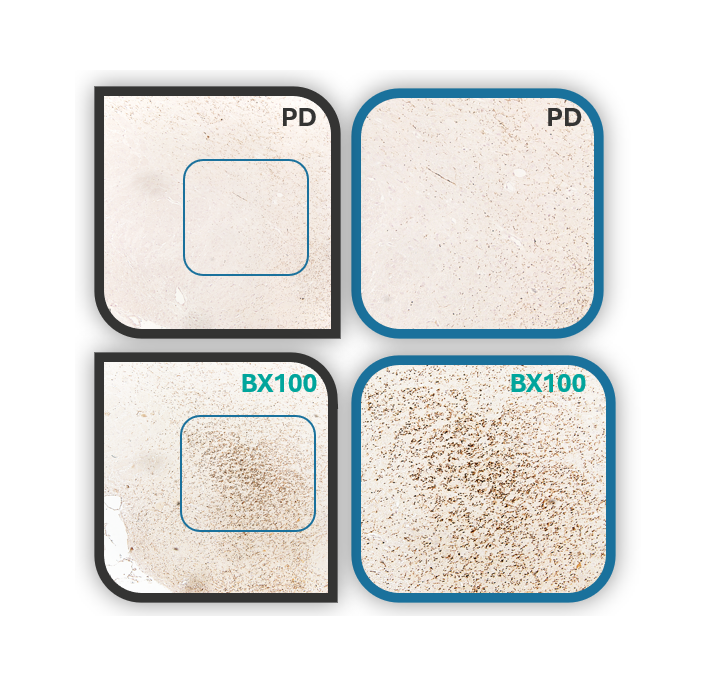

- In 2016, Chairman Vincent Chiang initiated a collaboration with Prof. Ying-Jui Ho from Chung Shan Medical University to develop a novel therapeutic candidate for Parkinson’s disease (PD), Parkinson’s disease dementia (PDD), and dementia with Lewy bodies (DLB). The project aims to address the underlying causes of these neurodegenerative disorders and to develop an innovative treatment capable of modifying disease progression.

- In 2017, an Investigational New Drug (IND) application was submitted to the U.S. FDA, enabling the launch of a multicenter, double-blind Phase II clinical trial in patients with PDD. The study progressed to the unblinding stage in the second quarter of 2025.